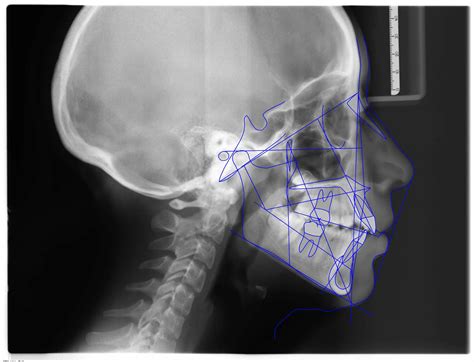

Radiografía Panorámica - Radiografía Lateral de Cráneo: Con esta radiografía, se obtienen los datos de la posición, el ángulo y la inclinación de los dientes y de los huesos maxilares. Con estos datos se realiza la Cefalometría de cada paciente, que es la medición de las relaciones de los maxilares, los dientes y las tendencias naturales del desarrollo craneofacial que hay que potenciar o corregir.

Radiografía Lateral de Cráneo

Software de Análisis Cefalométricos

Algunas clínicas, como MARFIL DEN, utilizan software especializado como NEMOTEC para el análisis digital de los registros de cada paciente. Este software permite realizar:

- Análisis de la estética facial: Ver las proporciones de la cara en los tres planos del espacio y detectar las posibles asimetrías.

- Análisis cefalométrico: Medir las relaciones de los huesos del cráneo a partir de una radiografía lateral de cráneo y compararlos con patrones de normalidad.